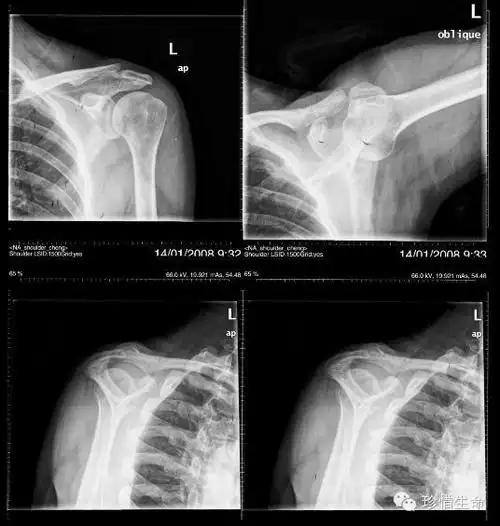

肩关节x线检查特殊体位

肩关节的摄影体位

肩关节x线检查体位大全

不同肩关节x线投照位